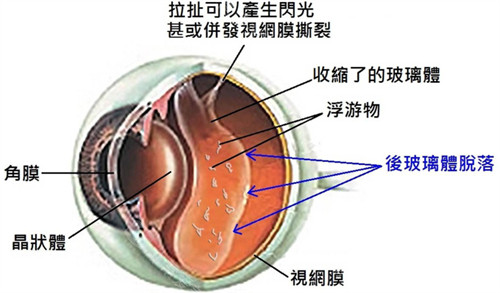

作为首都医学大学附属北京同仁医院眼底病科的“定海神针”,他擅长复杂眼底病诊疗,尤其对视网膜脱离、糖尿病视网膜病变等疾病的手术处理堪称业内标杆。